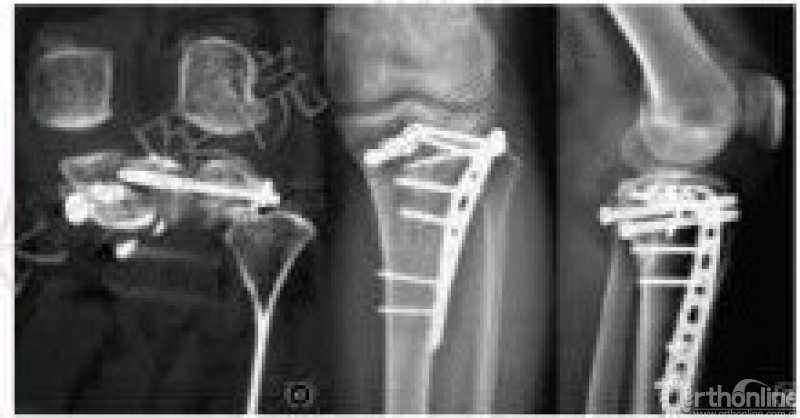

1. 腓骨头截骨

2010年

2008年禹宝庆

适用于41B2.1x或u并t,41B3.1x或u并t。

这种方法单独或结合后内侧入路治疗胫骨平台骨折8例。

2. 腓骨颈截骨入路1

2012年庄岩

原文:17例胫骨平台后外侧骨折患者。膝关节外侧经腓骨头的纵形切口,近端起自腓骨头上方10cm,向远端垂直延伸10-15cm。

腓骨颈截骨入路2

2016年

原文:15例患者采用腓骨颈截骨术,6例患者需要Gerdy结节截骨。所有骨折和截骨均愈合。解剖复位16例。

3. 腓骨头二腹肌截骨

2015年纽约特种外科医院

与腓骨头截骨术相似。

原文:采用标准的前外侧入路,但皮肤和筋膜切口向后移,在Gerdy结节和腓骨头之间分开。

4.股骨外髁截骨入路

2014年

采用垂直前外侧切口。